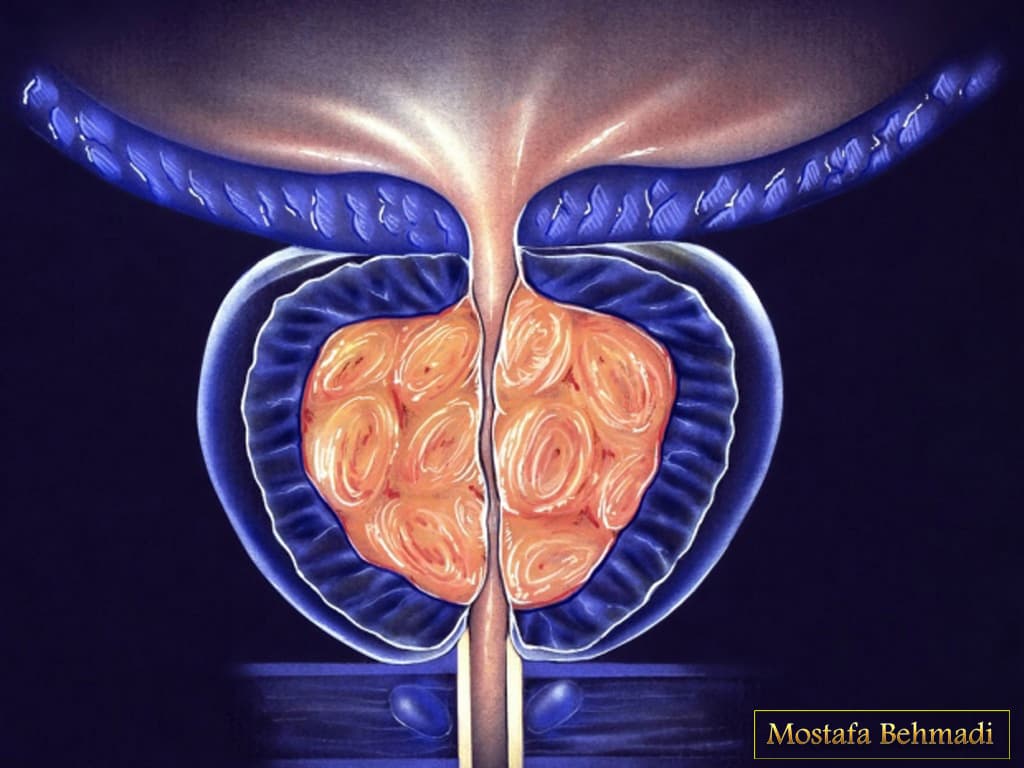

ساختار و عملکرد غده پروستات

پروستات غده ای در دستگاه تناسلی مردان است. این غده در لگن زیر مثانه و جلوی راست روده قرار دارد. پروستات در ساخت و ذخیره ی مایع منی نقش دارد. اندازه ی متوسط پروستات مشابه گردو است و اگر این غده بیش از مقدار طبیعی رشد کند و سرطانی شود دفع ادرار را کند می کند چون قسمتی از پیشابراه از غده پروستات می گذرد.